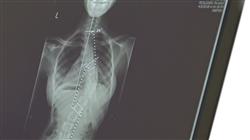

Há uma tendência crescente de subespecialização nas especialidades médico-cirúrgicas, uma questão relevante também na cirurgia da coluna, devido à ampla variedade de lesões que ela abrange. Por isso, a necessidade de um programa científico completo e de alta qualidade para ajudar e orientar neste campo tão específico e apaixonante, mas, acima de tudo, com uma capacitação prática que permita seu desenvolvimento em situações reais. Graças a este programa em Cirurgia da Coluna Vertebral, o médico poderá dominará tanto os aspectos básicos da especialidade quanto os novos avanços técnicos neste campo. Para conseguir isso, se unirá a uma equipe médica de qualidade em um hospital líder na área por 3 semanas, acompanhado por um orientador designado.

Aproximadamente 70 a 85% da população adulta sofre de dor nas costas em algum momento de suas vidas. Por esta razão, a cirurgia coluna vertebral é uma das mais buscadas no setor. Este tipo de intervenção é uma das mais complexas, avançadas e delicadas. Por esse motivo, é de vital importância que os cirurgiões estejam constantemente atualizados com os tratamentos mais recentes para as diferentes patologias da coluna vertebral.

Com este programa de capacitação, os médicos terão uma visão geral completa das patologias da coluna vertebral e todos os avanços em termos de métodos diagnósticos e terapêuticos para lidar com esse tipo de procedimento, bem como os avanços no tratamento de fraturas vertebrais, entre outros casos no campo da patologia da coluna vertebral. Para isso, eles terão a oportunidade de aprender sobre a prática cirúrgica e os aspectos que afetam diretamente a qualidade de vida dos pacientes, além de melhorar seu desempenho na área.

Esta Capacitação prática em Cirurgia da Coluna Vertebral abrangerá as práticas clássicas e usuais utilizadas em centros cirúrgicos especializados, bem como as técnicas cirúrgicas que atualmente estão definindo tendências no setor. Isso permitirá que o profissional, além de ampliar seu conhecimento pessoal, seja capaz de aplicá-lo com mais confiança e habilidade ao tomar decisões em sua prática clínica diária. É fundamental que os médicos sejam capazes de responder adequadamente aos casos que lhes são solicitados, fornecendo o conhecimento científico e tecnológico mais apropriado.

A Capacitação Prática em Cirurgia de Coluna Vertebral é um dos programas de pós-graduação mais valiosos que um médico pode seguir se deseja se especializar nesta área da medicina. Este estudo foi projetado para preparar os médicos para desempenhar um papel significativo na realização de procedimentos complexos na coluna vertebral e no atendimento a pacientes com condições relacionadas à coluna. A TECH Global University foca em fornecer conhecimentos atualizados e eficazes no âmbito profissional. Os cursos abordam os princípios básicos da anatomia da coluna vertebral, as técnicas cirúrgicas utilizadas no manejo das condições da coluna, a avaliação pré-cirúrgica e pós-cirúrgica dos pacientes e o atendimento ao paciente durante o período de recuperação.